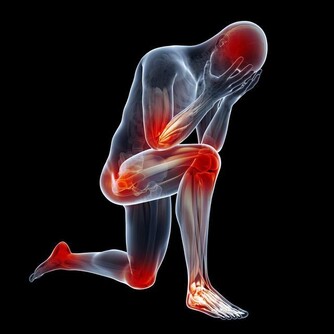

我們知道膝蓋是我身體的一個重要的組成部分,

只有擁有一個健全的完好的膝蓋我們才能夠讓自己活的更加的年輕,

在平時的生活中才能夠步伐更加的強勁有力。

在美國,每年有高達900多萬人去骨科就診,其中大部分都是出於膝蓋的不適。

膝蓋的天敵

1.年齡

早在青少年時期,關節軟骨就開始退化,

骨關節炎開始趁機蠢蠢欲動。

隨著年齡增長,血液循環及肌肉變弱,

關節部位因潤滑液分泌減少而變干,

軟組織的彈性減弱,更易受到拉傷的威脅,

同時軟骨變得易砰易剝落;

半月板也開始退化並缺乏重建的能力,

這個問題因體重增加而惡化。